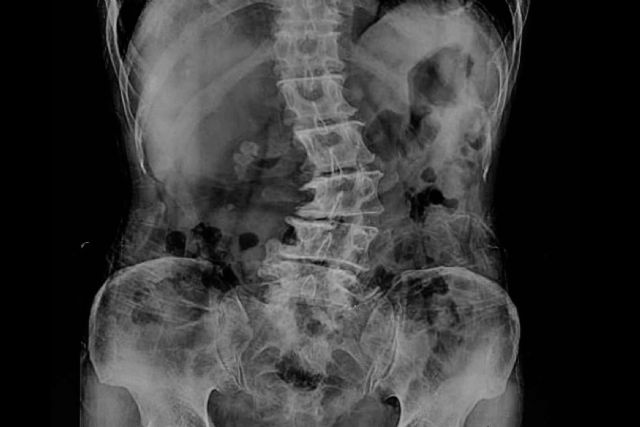

De acuerdo con los expertos de Biziondo, la escoliosis lumbar es una deformidad de la columna que se caracteriza por una curvatura lateral de la misma, provocando que adopte una forma de S o de C. Esta condición puede generarse como resultado de factores genéticos, enfermedades neuromusculares o lesiones en la parte inferior de la columna vertebral.

Para diagnosticar la escoliosis lumbar, los profesionales de la unidad médica Biziondo pueden llevar a cabo un examen físico, una radiografía de la columna vertebral o una resonancia magnética. En ese sentido, lo ideal es obtener un diagnóstico temprano mediante un examen médico, con la finalidad de prevenir la aparición de complicaciones a largo plazo.